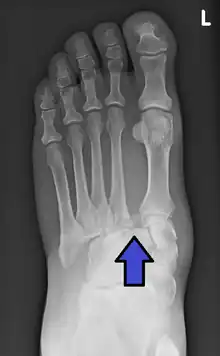

| An X-ray of a Lisfranc injury | |

In a high energy injury to the midfoot, such as a fall from a height or a motor vehicle accident, the diagnosis of a Lisfranc injury should, in theory at least, pose less of a challenge. There will be deformity of the midfoot and X-ray abnormalities should be obvious. Further, the nature of the injury will create heightened clinical suspicion and there may even be disruption of the overlying skin and compromise of the blood supply. Typical X-ray findings would include a gap between the base of the first and second toes.[8] The diagnosis becomes more challenging in the case of low energy incidents, such as might occur with a twisting injury on the racquetball court, or when an American Football lineman is forced back upon a foot that is already in a fully plantar flexed position. Then, there may only be complaint of inability to bear weight and some mild swelling of the forefoot or midfoot. Bruising of the arch has been described as diagnostic in these circumstances but may well be absent.[9] Typically, conventional radiography of the foot is utilized with standard non-weight bearing views, supplemented by weight bearing views which may demonstrate widening of the interval between the first and second toes, if the initial views fail to show abnormality. Unfortunately, radiographs in such circumstances have a sensitivity of 50% when non-weight bearing and 85% when weight bearing, meaning that they will appear normal in 15% of cases where a Lisfranc injury actually exists.[10] In the case of apparently normal x-rays, if clinical suspicion remains, advanced imaging such as magnetic resonance imaging (MRI) or computed tomography (CT scan) is a logical next step.[11]